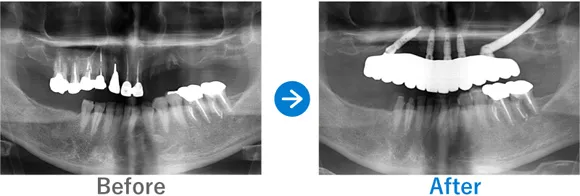

Case3

重度の歯周病を罹患された方。フルマウスインプラント治療直後に仮歯が入り感動されたケース

全顎上下共にブリッジ治療されている。重度の歯周病で歯がグラグラしている。

上下、ALLON4

5,884,000円(上下総額/内訳:上顎オールオン4(ノーベルインプラント4本)、下顎オールオン4(ノーベルインプラント4本)、3Dモデルガイド*、仮歯、セデーション、ボツリヌストキシン注射、3D模型、保証10年)

来院の背景

全体的に重度の歯周病に罹患しており、歯がグラグラしており抜けそうで咬めない、食事ができなく困っていた。インプラントを検討していたが他院で800万円〜900万円と聞いた。デンタルローンを申請。

治療結果

上下のALLON4を実施して治療同日に上下手術を行った。治療後すぐに仮歯が入ったので、とても喜んでいただいた。治療終了。メンテナンス来院継続中。

現在、セルフケアもしっかりされていて、メンテナンスも欠かさず来院していただいているため、インプラントは問題なく使えています。先日、横浜院で10年ぶりくらいにお会いしたのでご挨拶したら、とても喜んでくださりました。あの時インプラントの決断をして良かったと仰っていました。